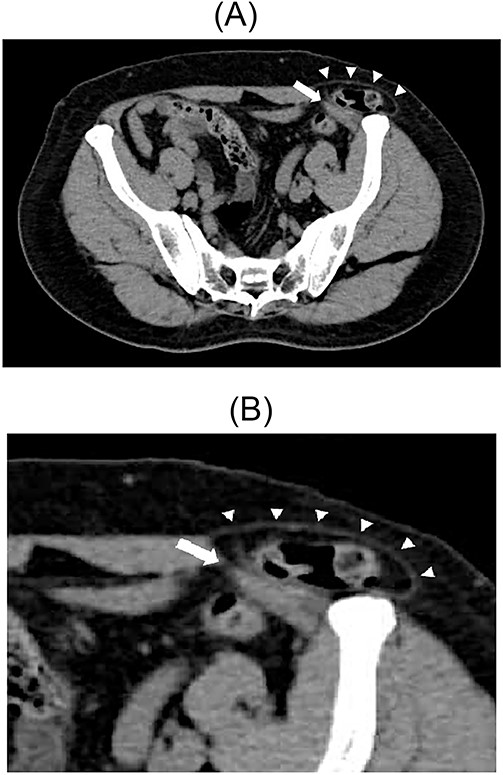

A 67-year-old male patient presented to the outpatient clinic with bilateral inguinal swelling and pain that had continued from a year prior. The swelling on the left side extended from the inguinal region toward the head. Based on the physical findings, we decided to perform CT. On the left side, contrast-enhanced CT scan revealed that a portion of the sigmoid colon protruded between internal and external oblique muscles passing near the spermatic cord. Furthermore, the sigmoid colon had prolapsed cranially from the hernial orifice. On the right side, prolapse of adipose tissue was observed (Fig. 5A and B). Therefore, the patient was diagnosed with a left interparietal inguinal hernia and right inguinal hernia. Based on this diagnosis, laparoscopic repair of both hernias was planned.

Contrast-enhanced CT scan; the sigmoid colon entered into the layer between the internal and external oblique muscles; the white arrow indicates the internal oblique muscle, and the white triangles indicate the external oblique muscle (A). Enlarged view of the inguinal region (B).